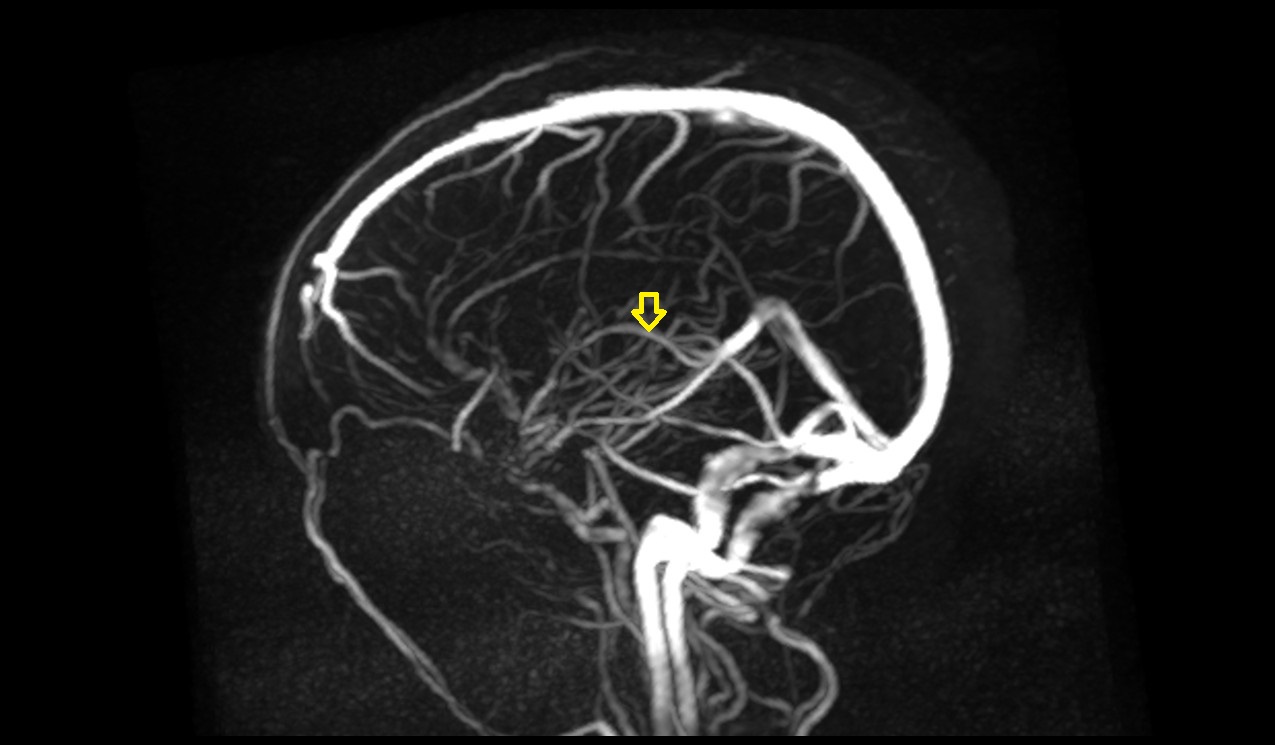

- Superior sagittal sinus